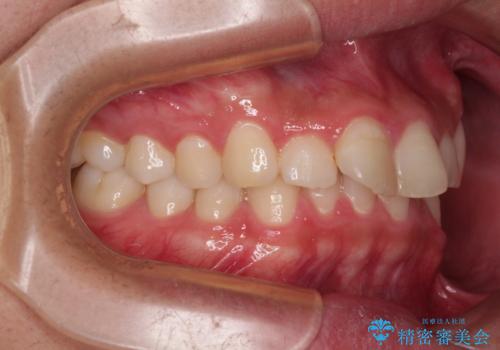

- ディープバイトと上顎前歯の突出、奥歯の咬み合わせを気にして来院された患者様です。

上顎歯列は全体的に前方位にあり、それが原因で深い咬み合わせとなり、突き上げにより上顎前歯が前方に飛び出している状態でした。

また、左右ともに上顎最後臼歯が頬側に転位している鋏状咬合となっていました。